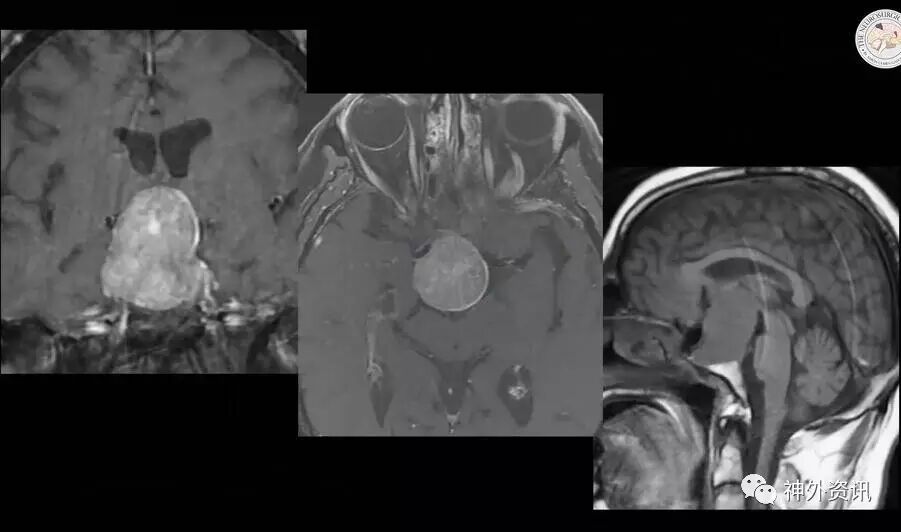

图1. 患者男性,53岁,视觉障碍。MR提示巨大垂体腺瘤,肿瘤质地相对不均,可能侵犯床突和斜坡区域。

53 year-old male with visual dysfunction

男性,53岁,视觉障碍

Let’s go ahead and discuss the case of such a patient. A 53 year-old male with visual dysfunction, who harbored this giant pituitary adenoma relatively heterogeneous and potentially eroding through the clinoid and the area of clivus.I use a standard thranssphenoidal approach.

让我们开始讨论这个病例。病人男性,53岁,视觉障碍;患有巨型垂体腺瘤,肿瘤质地相对不均,可能侵犯床突和斜坡区域。我使用标准的经蝶入路。